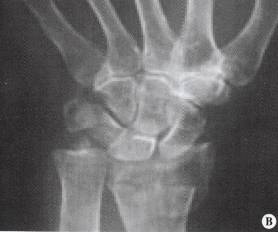

3、桡骨远端关节面骨折伴腕关节脱位

桡骨远端关节面骨折伴腕关节脱位 (Barton 骨折) 是桡骨远端骨折的一种特殊类型。

在腕背伸、前臂旋前位跌倒, 手掌着地, 暴力通过腕骨传导, 撞击桡骨关节背侧发生骨折, 腕关节也随之而向背侧移位。

其发生率占全身骨折的 0.1%。临床上表现为与 Colles 折相似的「银叉畸形」及相应的体征。

X 线拍片可发现典型的移位。当跌倒时, 腕关节屈曲、手背着地受伤, 可发生与上述相反的桡骨远端掌侧关节面骨折及腕骨向掌侧移位。

这类骨折较少见, 临床上常漏诊或错误诊断为腕关节脱位。只要仔细阅读 X 线片, 诊断并不困难。